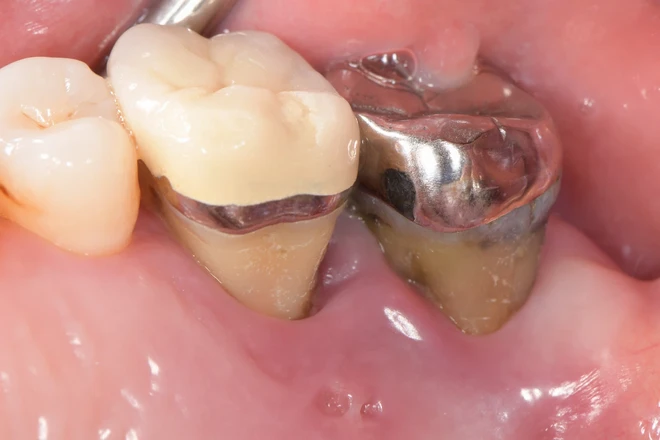

一名50歲患者,這幾個月以來,右側上顎第一大臼齒與第二大臼齒出現嚴重疼痛及非常大的動搖度,醫師檢查發現為牙周病導致牙槽脊破壞嚴重,建議拔除這2顆牙齒。由於病人擔心拔牙後齒槽脊會嚴重塌陷導致植牙困難,無法再擁有良好的咀嚼功能,一度讓他憂心抗拒拔牙⋯⋯

奇美醫院牙周病科主治醫師李芳欣說明,牙周病是一種常見的口腔疾病,由於牙菌斑及牙結石的堆積,導致牙齦發炎,進而破壞齒槽骨。齒槽脊是支撐牙齒的重要結構,若因牙周病而受損,易導致牙齒鬆動甚至脫落,嚴重影響口腔健康與生活品質,且拔牙後齒槽脊也會嚴重萎縮,造成後續假牙重建變得困難。

右側上顎第一和第二大臼齒嚴重牙周病破壞,牙肉和骨頭塌陷。(圖片來源:奇美醫院)